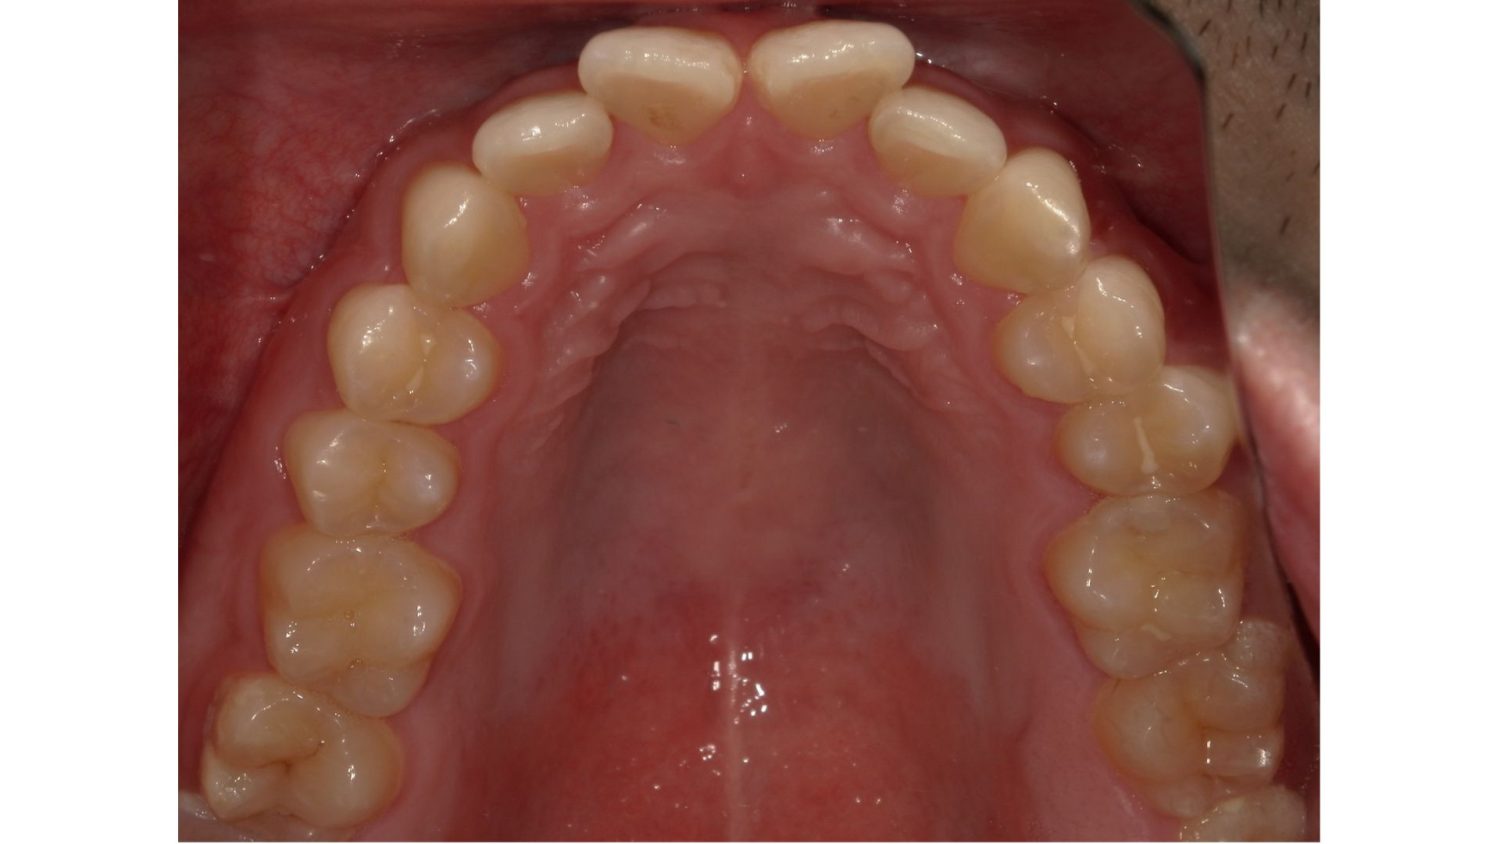

前歯だけの矯正の症例紹介①

Before

主訴

前歯の歯並びをキレイにしたい。

治療内容

ワイヤー矯正で治しました。

治療費

115,500円(税込)(リテーナー込み)

治療期間

2か月

通院回数

4回

想定されたリスク

※ブラックトライアングルができる可能性がありました。

多少ブラックトライアングルができたのでゴムを用いて閉鎖しました。比較的短期間で改善した症例です。